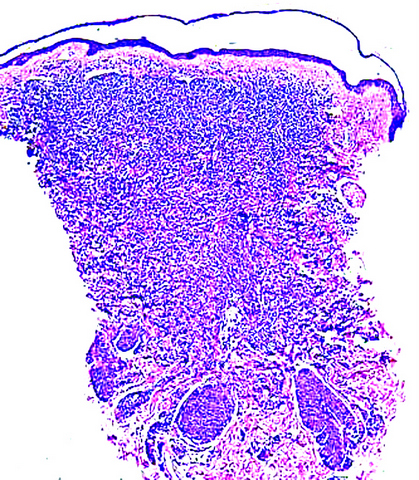

Microscopic (histologic) description

- Within the macules and plaque, mast cells are predominantly in papillary dermis

- Mast cells are round or spindle shaped with abundant eosinophilic cytoplasm, distinct cytoplasmic boundaries, large pale nuclei

- Eosinophils are often present

- Also edema of papillary dermis, subepidermal vesiculation

- Bullous mastocytosis may be diagnosed by Tzank smear; infiltrate may be slight and perivascular

- In telangiectasia macularis eruptive perstans, features may be subtle, with increased mast cells around dilated superficial capillaries, basal cell hyperpigmentation of overlying epidermis, superficial lymphohistiocytic infiltrate

Microscopic (histologic) images